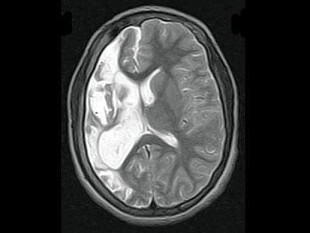

男,35岁,有颅脑外伤史,MRI图像,最可能的诊断是()

• A.脑软化

• B.脑萎缩

• C.脑积水

• D.脑穿通畸形囊肿

• E.脑实质占位